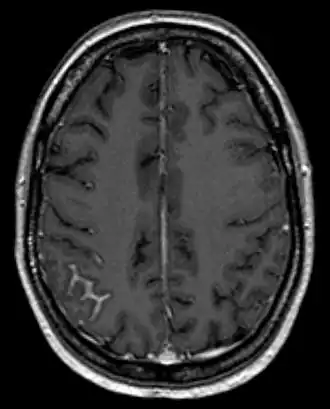

Первым диагностическим шагом для распознавания карциноматоза является МРТ головного и спинного мозга. Чувствительность методики около 70%, особенно при распознавании адгезивной формы. МРТ следует проводить до пунктирования спинномозговой жидкости, так как последняя вызывает реакцию оболочек, которая в МРТ может быть неправильно истолкована. Исследование спинномозговой жидкости может потребоваться для диагностики неадгезивной формы карциноматоза - доказательством последнего служит обнаружение опухолевых клеток в спинномозговой жидкости, что происходит только в 50% случаев при первой пункции, после трех пункций вероятность обнаружения клеток лежит около 90%[4].